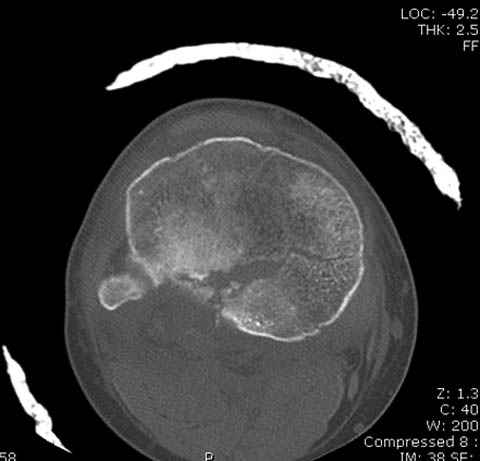

Здесь как раз тот случай, когда результат зависит не только от мастерства хирурга, но и от наличия современных методов исследования. Например, КТ которая поможет рассчитать направления шурупов и установку импланта. Кроме этого, поможет определиться с доступом.

На представленных предоперационных срезах КТ огромный задне-медиальный фрагмент расположен больше кзади, чем медиально. Для планирования, кроме поперечных срезов, надо ориентироваться на корональные срезы, которые укажут топографию верхушки медиального фрагмента.